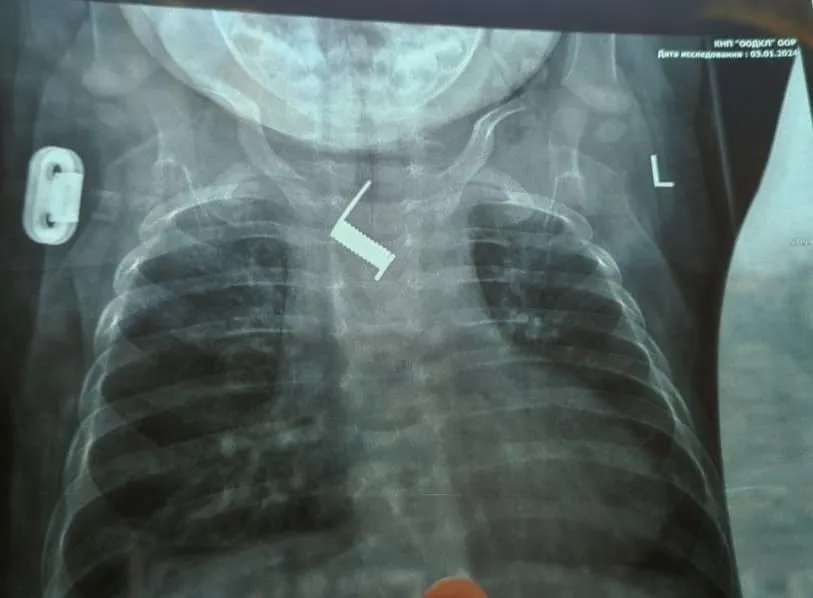

В Одесской областной детской клинической больнице медики спасли жизнь младенцу, который проглотил пружину. Врачи извлекли посторонний предмет из пищевода ребенка.

Пружину из пищевода шестимесячного ребенка извлекли с помощью эндоскопии в отделении инструментальных методов исследования и лечения. Врачи рассказали, что ребенка амбулаторно лечили в районной больнице от бронхита и пневмонии в течение двух недель. После того, как состояние маленького пациента не улучшалось, его госпитализировали в областную детскую больницу.

Медики отметили, что через две недели пружина почти вросла в стенку пищевода младенца. После прибытия в стационар больницы была выполнена обзорная рентгенограмма, по результатам которой был обнаружен посторонний предмет в теле ребенка, а именно пружинку от шпильки для волос.

"Находилось постороннее тело на уровне средней трети пищевода, наряду с дугой аорты. Инородное тело было удалено эндоскопически, что избавило ребенка от тяжелого хирургического вмешательства и рисков для жизни", - рассказали медики.